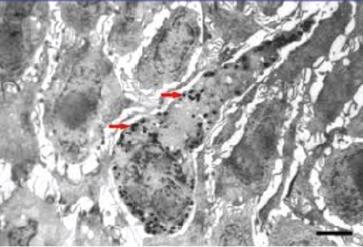

Sähköinen mikroskooppikuva melanosyytistä johon on merkitty punaisin nuolin melaniinipigmenttipaketit.

Luonto on suunnitellut melaniinin antamaan jonkinlaista suojaa uv-valon aiheuttamia haittoja vastaan. Sekä UVAettä UVB-säteet aiheuttavat vapaiden radikaalien aiheuttamia tuhoja iholla päiväsaikaan huolimatta siitä paistaako aurinko vaiko ei. Ihomme joutuu aina säteiden pommittamaksi. UVA-säteet pääsevät ikkunalasienkin läpi. Jatkuva altistuminen säteille aiheuttaa näkyviä ja biokemikaalisia ikääntymisen merkkejä ja lisäävät syöpäriskiä. Kuparilla on tärkeä merkitys melaniinisynteesissä melanosyyteissä joita on ympäriinsä tyvikalvovyöhykkeellä epidermiksen alaosassa. Tyrosinaasi, joka on kuparin entsymaattinen kumppani, on tärkein

entsyymin melaniinisynteesissä ja sen tehtävänä on rajoittaa melaniinin tuotantoa.